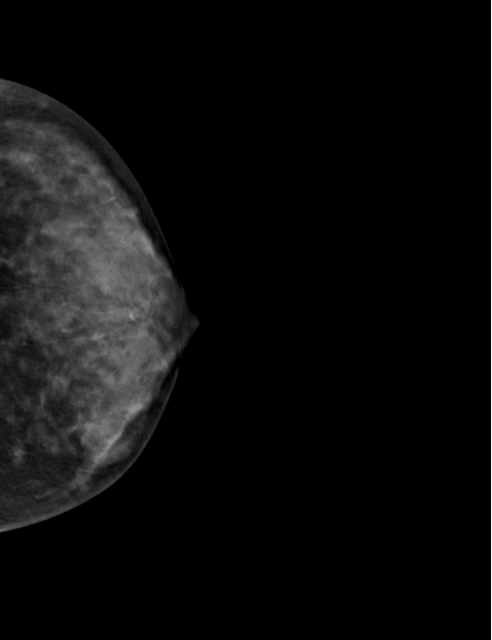

HOLOGIC Selenia Dimension

2D 유방촬영술

• 국가 암 검진 검사

• 만 40세 이상 2년마다 필요 항목

3D 유방촬영술

• 신의료기술 등재

• 치밀 유방 환자에서 중첩되어 가려지는 병변 확인에 유용